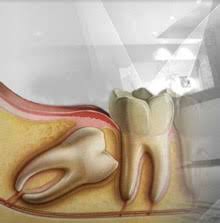

Von der Wuchsrichtung des Zahnes davon wie viel von dem jeweiligen Zahn bereits im Kiefer angelegt und verwachsen war und. Verläuft der Durchbruch der Weisheitszähne bei einigen Menschen ohne Komplikationen so leiden andere unter starken Schmerzen und Entzündungen die sich über mehrere Monate hinweg ziehen. Schmerzen nach dem Ziehen der Weisheitszähne.

Wie stark die Schmerzen sind und wie lange sie andauern hängt von einigen Faktoren ab. Dann allerdings sollten diese langsam abklingen. Bei den meisten Entfernungen der Weisheitszähne entstehen nur leichte Schmerzen oft hat man überhaupt keine.

Es dauert je nach der Größe des Weisheitszahns und sonstigen Faktoren recht lange bis die Wunde vollständig verheilt ist. Das durchschnittliche Alter in dem die Weisheitszähne durchbrechen beträgt etwa 16 Jahre. Es kann 7-14 Tage dauern bis sie vollständig abklingen.